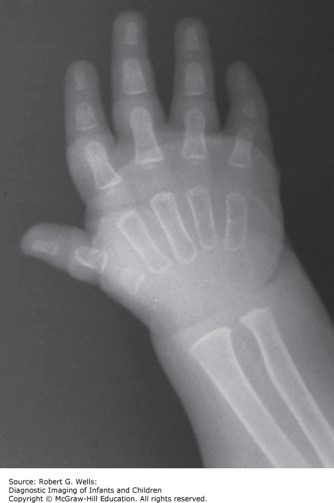

The patient has a low hairline, synophrys, arched eyebrows, long eyelashes, a thin upper lip and low-set ears. In examining the patient's extremities, you note spade like hands, 2–3 syndactyly of toes.

The correct answer is C. This patient most likely has Cornelia de Lange syndrome.

Photo: Wells RG. Diagnostic Imaging of Infants and Children; 2015.